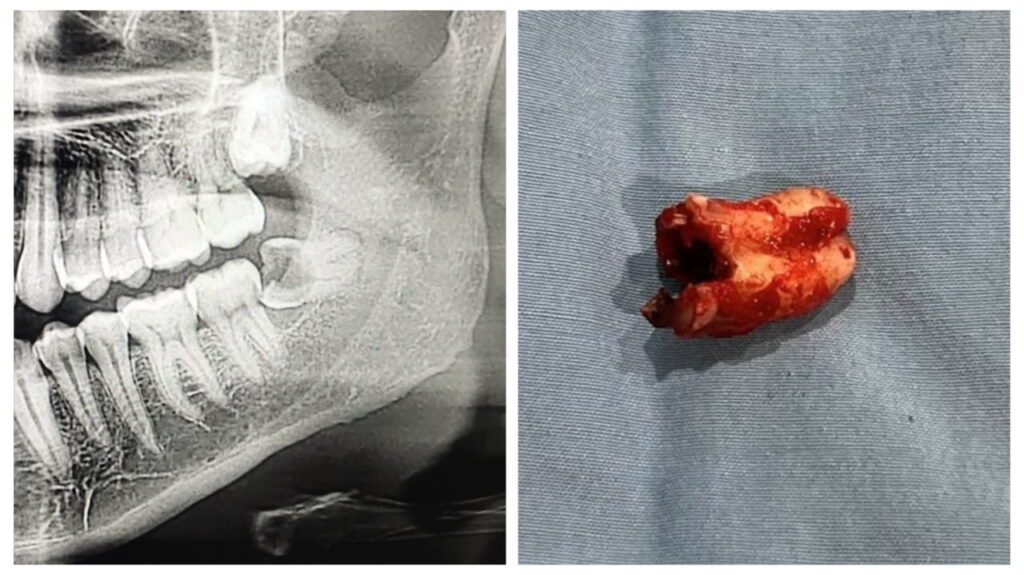

Surgical Removal Of Impacted Teeth